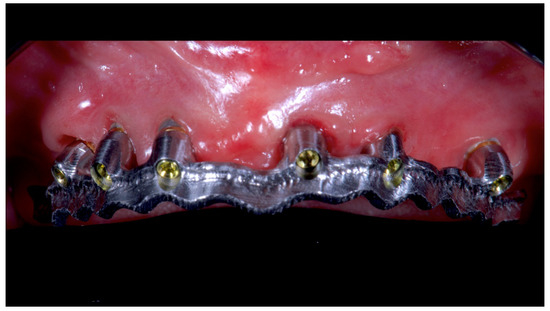

Figure 5.

Intraoral picture of the implant positions and the multi-unit abutment screwed on.